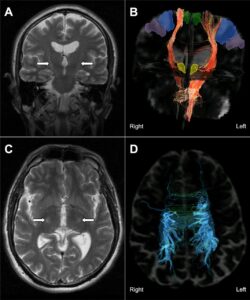

- EEG signals suggested improved brain activity patterns associated with ALS.